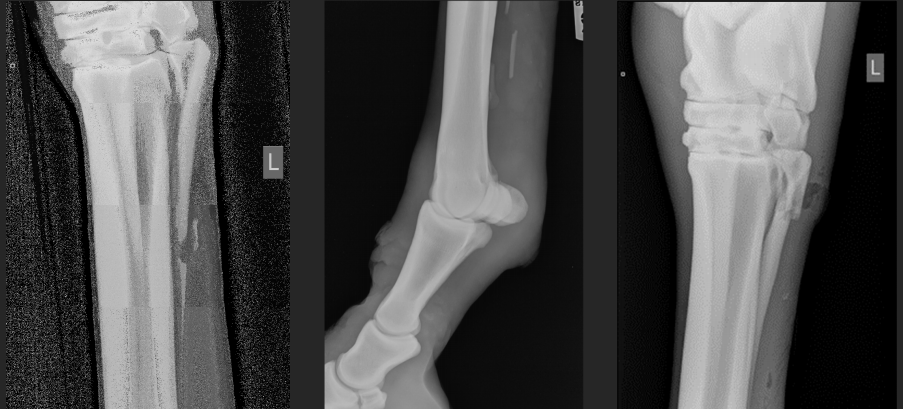

incomplete ossification in a young animal